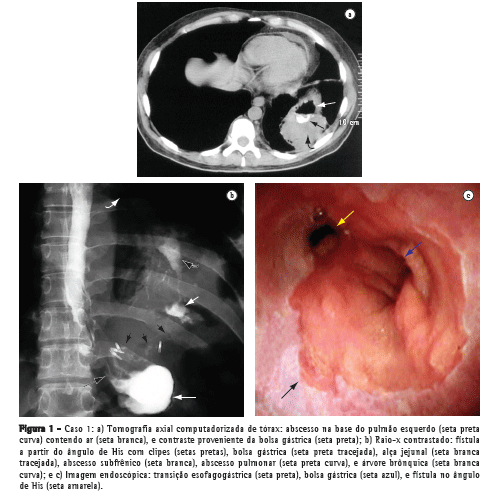

Uma paciente com 44 anos de idade foi submetida à gastroplastia vertical com anel (sleeve gastrectomy) por videolaparoscopia, evoluindo com fístula gástrica e cinco episódios de abscesso subfrênico durante 8 meses. Seu quadro clínico se iniciava com dor no ombro esquerdo e evoluía com febre, tosse, leucocitose, queda do estado geral e perda de peso excessiva. Os dois últimos episódios foram acompanhados de tosse com expectoração purulenta e a tomografia axial computadorizada de tórax diagnosticou abscesso na base pulmonar esquerda (Figura 2a), secundário a abscesso subfrênico a partir do ângulo de His, e estenose gástrica ao nível do anel e da incisura angularis. O abscesso pulmonar proveniente da fístula gastrobrônquica foi drenado através de cateter visualizado em radiografia contrastada (Figura 2b) e a imagem endoscópica mostra o orifício interno da fístula no ângulo de His (Figura 2c).

A paciente recebeu acompanhamento especializado de um pneumologista, um endoscopista e um cirurgião, sendo tratada por meio de antibioticoterapia, fisioterapia respiratória e suporte nutricional por sonda nasoenteral. Além disso, foi submetida a uma laparoscopia exploradora para retirada do anel, quando foi evidenciado um intenso bloqueio inflamatório na região subfrênica esquerda e na transição esofagogástrica o qual impossibilitava a abordagem cirúrgica da fístula.

Assim, foram realizadas seis sessões endoscópicas de estenostomia com bisturi elétrico e dilatação da área estenótica, o que permitiu a ingestão satisfatória de alimentos, o restabelecimento nutricional e a cicatrização do abscesso pulmonar, após o fechamento

definitivo da fístula.